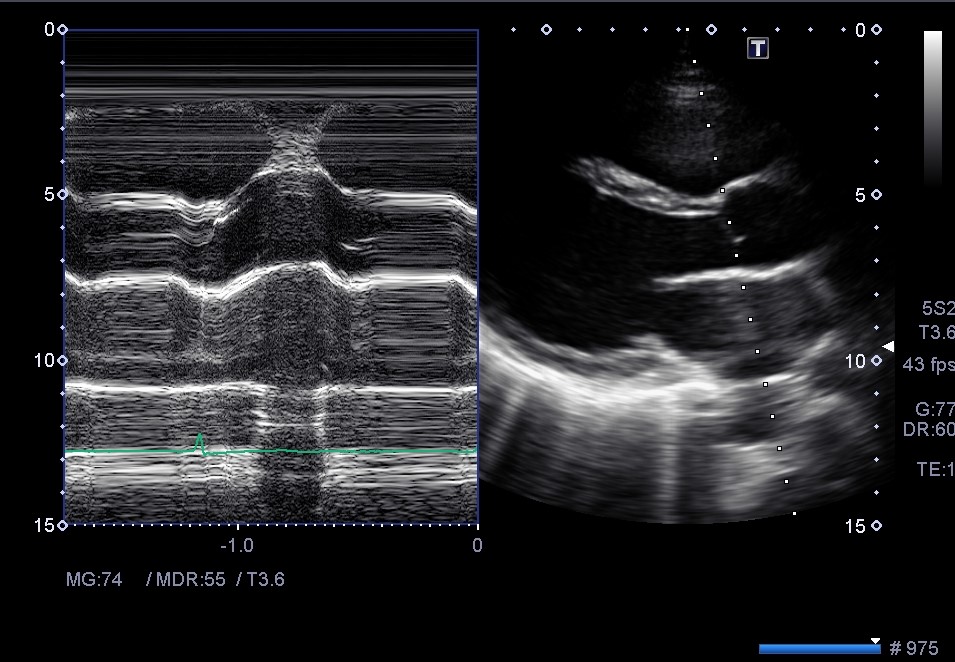

③

Bモードが綺麗に描出されている。

Mモードのラインがやや斜めなので、プローブを少し胸骨に近づけてみる。